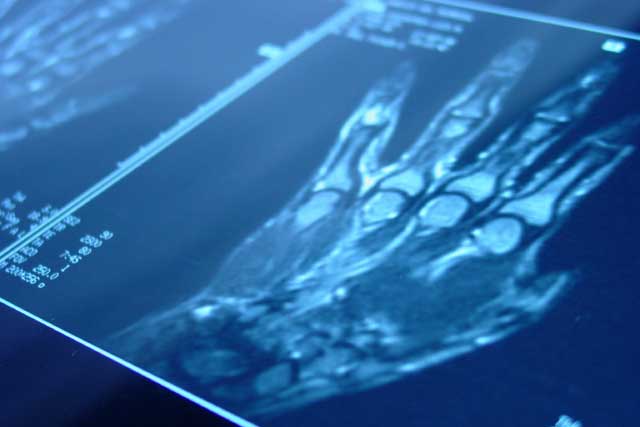

The Nuffield Orthopaedic Centre has a national and international reputation as a centre of excellence, and patients are referred from the UK and abroad for advice and management of their hand and wrist problems.